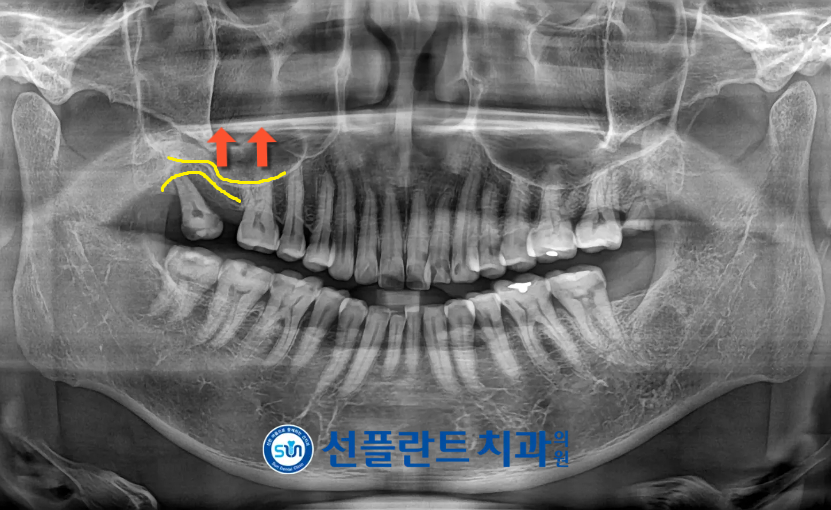

정밀한 상담을 위해

파노라마 사진을 촬영해 보았더니

보라색 화살표 표시의

위턱 양측 사랑니(#18,28)는

발치가 필요한 상황이었으며,

노란색 동그라미 표시의

위턱 앞니와 아래턱 양측 어금니 부위는

충치가 심한 상태로

크라운 보철물 수복이 필요하였는데요.

환자분과 정밀한 상담을 통해

불필요한 위턱 양측 사랑니는

발치를 진행하기로 하였으며,

빨간색 동그라미 표시의

상실되어 있는

위턱 오른쪽 두 번째 큰 어금니(#17)에는

임플란트 식립을 통해

치아의 기능을 회복시켜 주기로 하였습니다.

.

크라운 수복을 진행하기로 하였으며,

신경 손상이 보이는 치아는

신경치료를 동반하여

크라운 수복을 진행하기로 하였습니다.

상악동 막이 내려와 있어

임플란트를 식립하기에

수직적인 거리가 부족하여

상악동 거상술이 필요한 상황으로